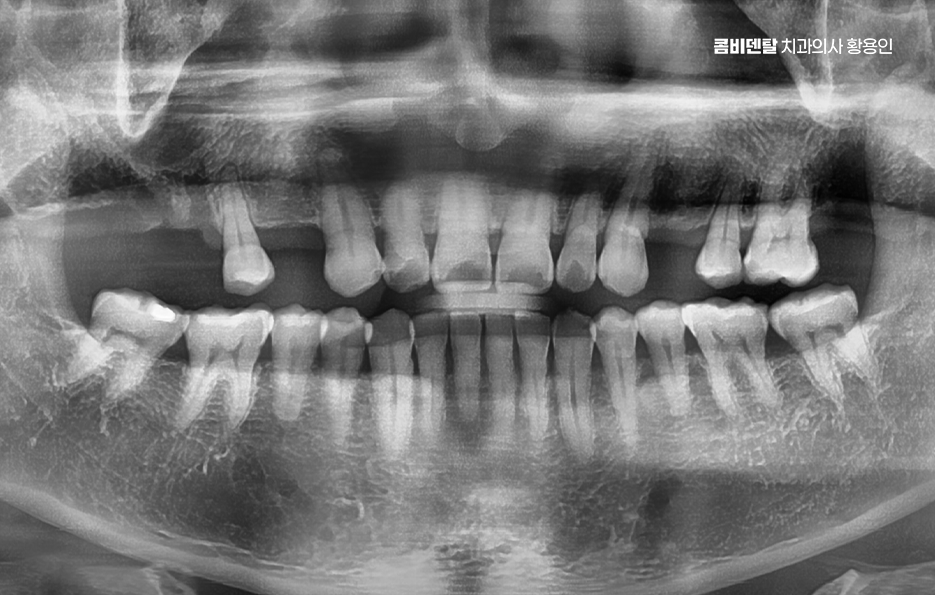

출처 아카이브 열기처음 어금니를 하나 잃었을 땐 그렇게까지 큰일은 아니라고 생각했어요. 충치가 너무 심해서 결국 발치를 하게 됐고, 치과 선생님은 빠진 자리를 임플란트로 채우는 게 좋겠다고 권하셨지만, 솔직히 당시엔 시간도, 돈도 여유가 없었고, 또 막상 하나쯤 없다고 해서 일상이 크게 불편하진 않았기 때문에 그냥 좀 불편하더라도 참자고 마음을 먹었어요. 한쪽으로만 씹는 습관이 생겼지만, 그건 생각보다 쉽게 적응됐고, 어금니 하나 없이도 밥을 먹는 데 큰 무리는 없다는 착각 속에서 점점 그 빈자리에 무뎌져 갔어요. 그렇게 몇 달, 몇 년이 흘렀고, 지금 와서 돌이켜보면 그때 치료를 미뤘던 결정이 얼마나 후회로 돌아오는지 스스로도 놀라울 정도예요. 처음 눈에 띈 변화는 반대쪽 어금니에 가해지는 압력이 점점 커졌다는 거였어요. 무의식적으로 계속 반대쪽만 사용하다 보니 그쪽 치아에 피로가 쌓이기 시작했고, 어느 날부터는 씹을 때 약간의 통증과 불편함이 느껴지기 시작했어요. 그때도 아직은 버틸 수 있다고 생각했어요. 통증이 있긴 해도 일시적일 거라 여겼고, 양치만 잘하면 괜찮아질 거라고 안일하게 넘겼어요. 그런데 문제는 그게 단순한 통증이 아니라 구조적인 불균형에서 시작된 거였다는 걸 늦게 깨달았어요. 빠진 어금니의 빈자리를 그대로 두면서 위쪽의 맞물리던 치아가 점점 내려오기 시작했고, 아래쪽 잇몸에 자극을 주기 시작하면서 잇몸이 자주 붓고 시큰거리는 현상이 생겼어요. 그뿐만 아니라 양옆에 있던 치아들이 빈 공간 쪽으로 기울기 시작하면서 음식물이 자주 끼고, 양치해도 개운하지 않은 날이 많아졌고, 결국 또다시 충치가 생기기 시작했어요. 하나의 치아를 잃은 게 끝이 아니라 주변 치아들까지 도미노처럼 영향을 받기 시작했다는 걸 그제서야 알게 된 거죠. 더 무서운 건 턱관절의 문제였어요.

이처럼 치아 상실 후에 임플란트에 대한 중요성을 느끼게 되는 것은 특히 앞니라면 인상을 좌우하는 위치이기 때문에 미루는 경우가 거의 없지만 어금니의 경우 반대편으로 씹으면 되지 않을까 하면서 치료를 미루는 경우가 많지만 어금니 없으면 얼굴 발음 및 편측 저작으로 인한 반대편 치아의 문제, 잇몸 뼈의 흡수 등 여러 문제로 이어질 수 있는데요

어금니는 단순히 음식을 씹는 역할만 하는 게 아니며 우리 턱과 얼굴을 지탱해주는 일종의 기둥 같은 존재로서 특히 아래 어금니는 턱뼈에 직접 연결되어 있어서 이 부분이 빠지면 턱뼈 자체가 빠르게 흡수되기 시작하고 뼈는 자극이 있어야 유지되는데 어금니가 없어진 자리엔 씹는 자극이 사라지니까 뼈가 점점 가라앉는 거예요.

더 심각한 건 치열 전체가 무너지는 것으로 어금니가 빠지고 그 자리를 비워 두면, 위에 맞물리는 치아가 점점 내려오거나, 옆 치아가 쓰러져 들어가며 이렇게 정출된 치아는 다시 제자리로 돌아오지 않기 때문에, 나중에 임플란트를 하려고 해도 공간이 맞지 않아서 교정치료를 먼저 해야 할 수도 있었어요.